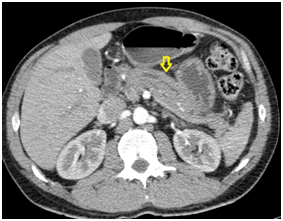

45-year-old man with no medical or surgical history, no alcohol or tobacco consumption, no known allergies or family medical history. With history of abdominal pain in the upper abdomen for about one year. Since one month ago referring with greater intensity in the left hypochondrium. The day of the consult pain intensifies up to 8/10 VAS with irradiation to the back. It was not associated with nausea, vomiting or jaundice. Patient was evaluated at the emergency department where he was found hemodynamically stable, afebrile, without jaundice, with no signs of peritoneal irritation and with diminished bowel sounds. Initial laboratory tests: hematocrit 42%, hemoglobin 14gr/dl, leukocytes 9000/uL, platelets 245000/uL, CRP 12mg/dl, AST 16 IU/ml, (35) ALT 27 IU/ml (50), ALP 65 IU/ml (70), GGT 28 IU/ml, total bilirubin 0.4mg/dl (1), Lipase 2744 U/L, Amylase 204 U/L. An abdominal CT scan was performed which showed peripancreatic edema and inflammatory changes of the peripancreatic adipose tissue (Figure 1). After initial study, mild acute pancreatitis was diagnosed. Biliary etiology was ruled out with an abdominal echotomography that showed a distended gallbladder with no stones, intra- and extra hepatic thin biliary tract. He had no drug or alcohol consumption and triglycerides were in normal range. Abdominal MRI showed a dilated pancreatic duct of 5mm, prominent pancreas and amputation of the pancreatic duct, without evidence of solid or cystic pancreatic lesion (Figure 2). Additional laboratory tests Ca19-9and serum IgG4 were within the normal ranges.

Figure 2 MRI cholangiography phase: amputation of the pancreatic duct.